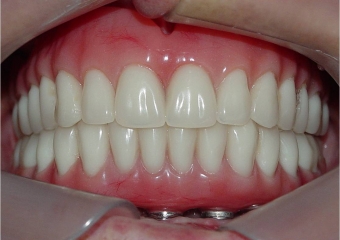

Prótese fixa inferior em resina instalada